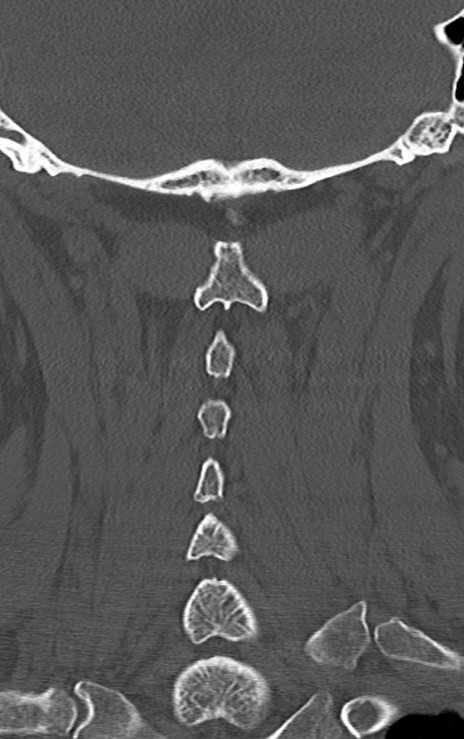

【整形】TIPS症例7 頚椎CT(冠状断像)

【症例】60歳代男性

【主訴】両手のしびれ

【現病歴】15年前より右手のしびれあり。4ヶ月前から左手のしびれあり。最近、症状増悪あり。

【身体所見】BTR+/+、BRR+/+、TTR+/+、PTR ++/++、ATR ++/++、Babinski-/

頚椎CT